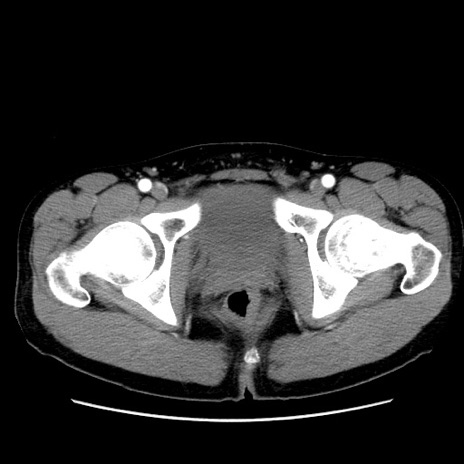

症例36(横断像)

【症例】20歳代 男性

【主訴】心窩部痛

【現病歴】今朝より上腹部痛あり。一旦軽快していたが再度出現したため救急要請。昨日夕に白身の魚を含む刺身を食べた。

【身体所見】BP 136/89mmHg、HR 74/min、BT 37.0℃、腹部:膨満、軟、心窩部に圧痛あり。反跳痛なし、筋性防御なし、腸雑音やや亢進あり。

【データ】WBC 17700、CRP 0.48